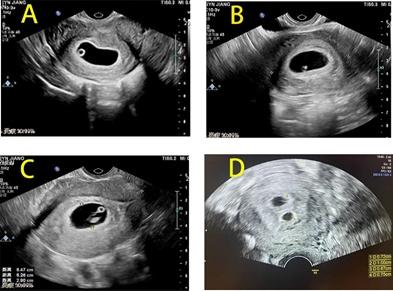

图1 四位怀孕困难女性早孕超声截图

怀孕5周以后,b超可看见小胎囊,胎囊约占宫腔不到1/4,或可见胎芽